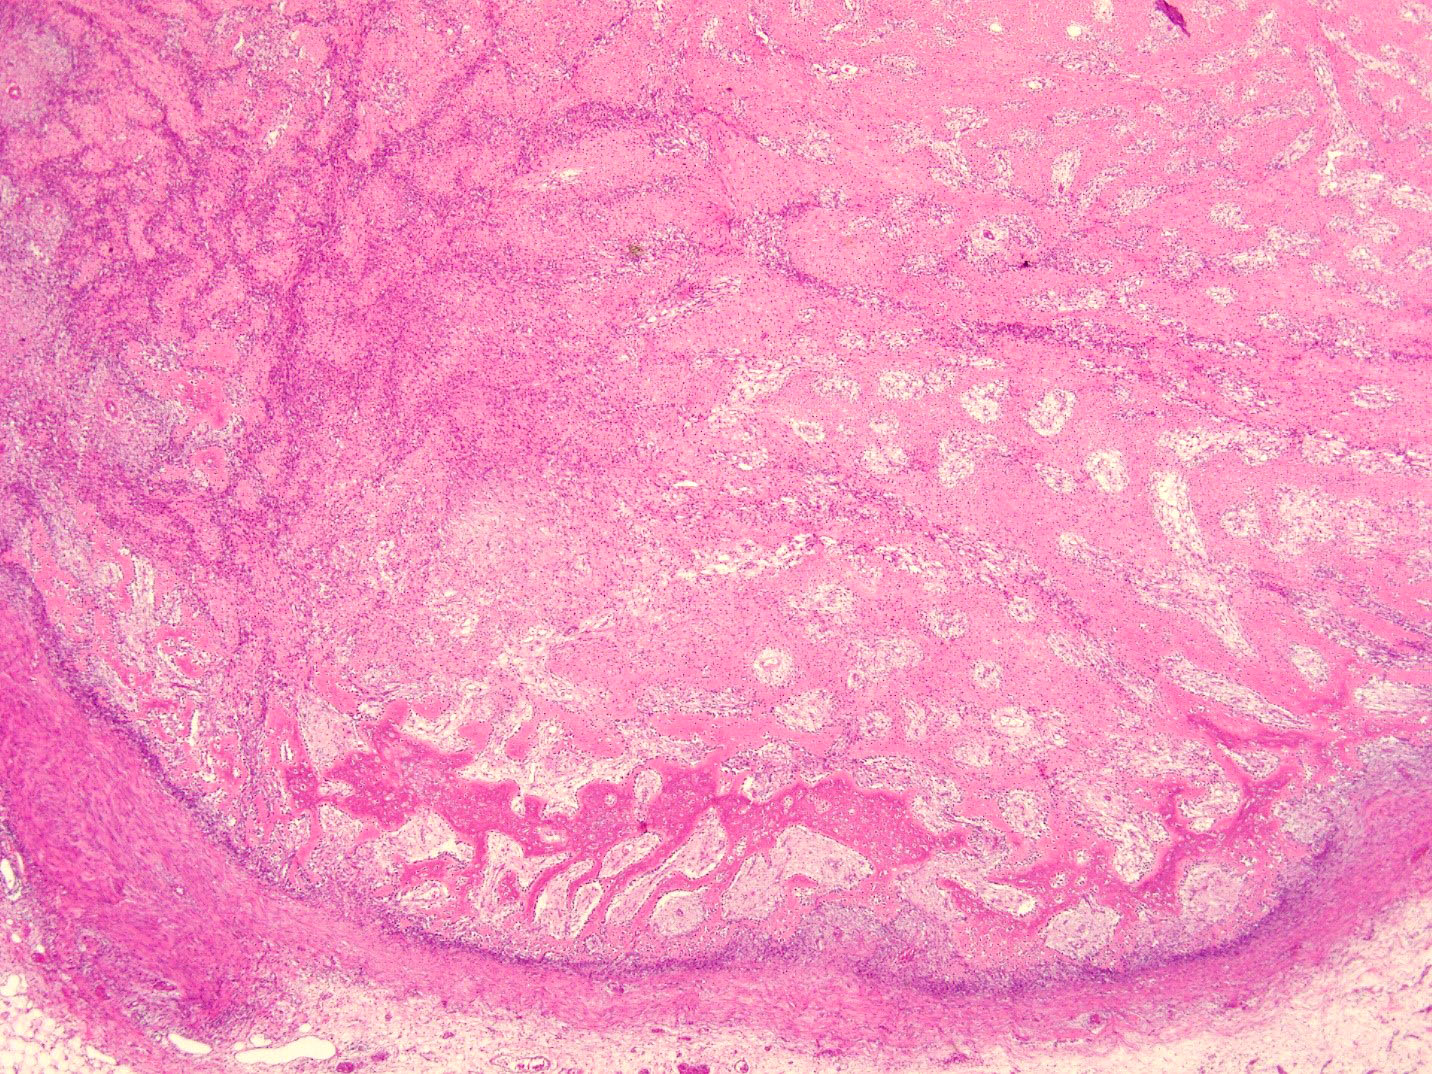

- Histologically, zonal pattern is characteristic with different degrees of cellular differentiation (inner zone, intermediate zone and peripheral zone)

- Peripheral zone:

- Osteoid undergoes calcification and leads to lamellar bone formation

- Islands of mature or immature cartilage may be present

- Extreme periphery / margin shows mature bone with osteoblastic rimming and little to no pleomorphism

- Lesion is separated from the normal tissue (muscle) by a zone of loose, myxoid fibrous tissue

- Late, mature stage (> 8 weeks):

- Mass is mostly composed of mature bone

- Very old lesions show only lamellar bone separated by fibrovascular stroma, mimicking osteoma

Microscopic (histologic) images

B. Myositis ossificans. The given history in this case shows that the patient is physically active and provides short duration history of the lesion. The radiological findings suggest a lesion with maturation at periphery. The microscopic image shows characteristic zonation. These are all features of myositis ossificans.